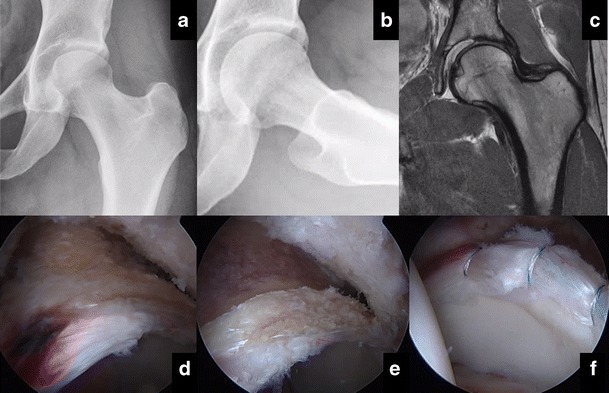

Fig. 2.

Predominant pincer-type FAI of the left hip in a 19-year-old catcher with hip pain. (A) AP and (B) Dunn-45° lateral XR revealing pincer deformity, negative Tӧnnis angle. (C) Anterosuperior labral tear with acetabular subchondral overload sclerosis but maintained cartilage. (D) Arthroscopic view of significant subspine and pincer deformities with hyperemic labrum and associated tear. (E) Acetabulum after pincer/subspine resection and (F) labral refixation